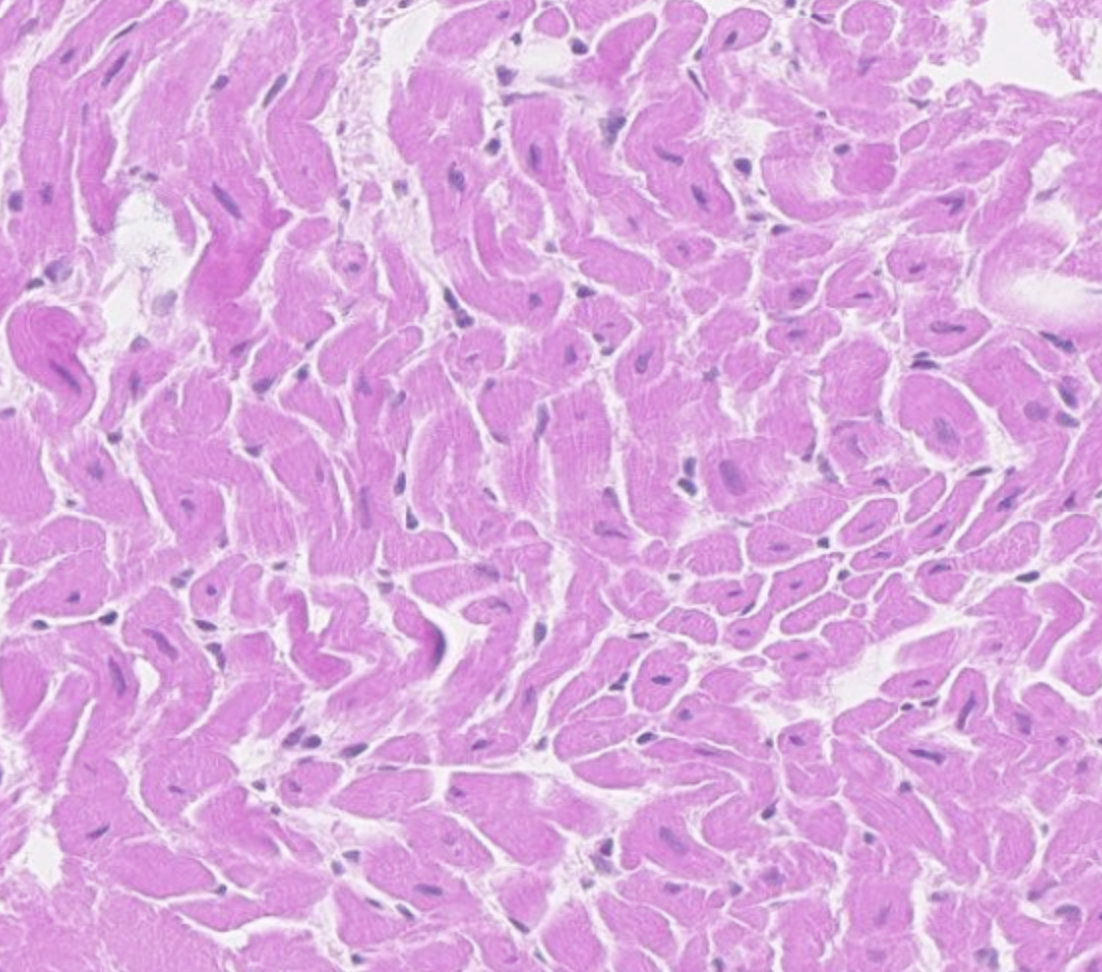

Wat voor type weefsel zie je hier?

A

Hartspierweefsel

Q

Hoe kan je hartspierweefsel van skeletspierweefsel onderscheiden?

Hartspierweefsel heeft glansstrepen, en de locatie van de nucleus is anders